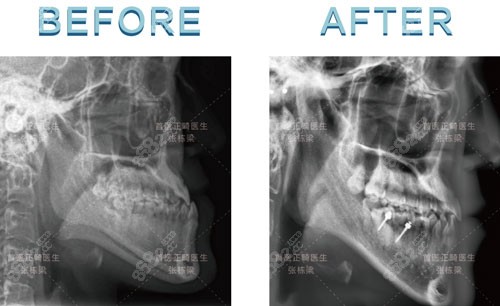

分享張棟梁疑難矯正案例:

術(shù)前分析:術(shù)前下巴前突,有點(diǎn)地包天,從CT片來看,屬于骨性前突,一般像這種情況都需要做正頜手術(shù)才行,但張棟梁通過正畸矯正,也能達(dá)到改善的效果。